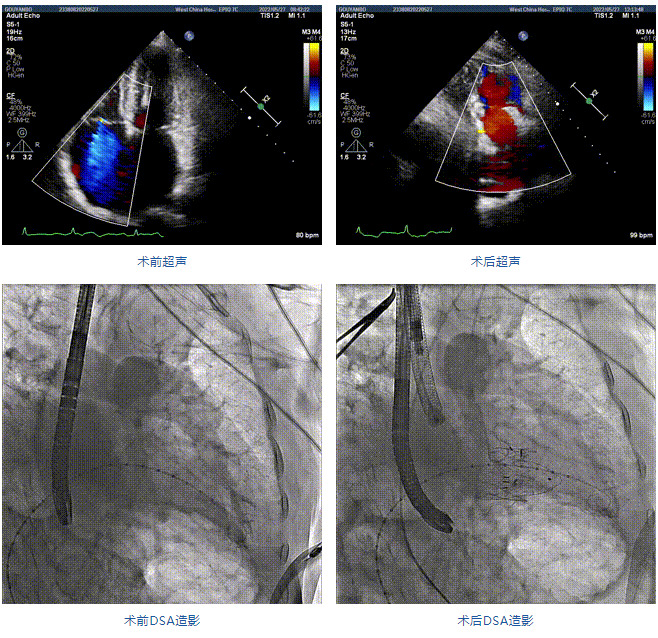

89歲男性。術前超聲報告顯示:雙房增大,左室壁肥厚,主、肺動脈增寬,三尖瓣重度反流。

團隊前期經過多次討論,制定了周密的手術策略和預案。由于患者已是近九旬的超高齡老人,傳統(tǒng)外科開胸手術風險極高,純介入經血管三尖瓣替換能夠明顯減少創(chuàng)傷。術中陳茂及馮沅教授結合體表定位在造影指示下精準穿刺右側頸靜脈并預置兩把血管縫合器。成功建立經皮血管入路后在食道超聲和DSA的引導下順利完成人工瓣膜植入,術后超聲和造影顯示人工三尖瓣同軸性良好,瓣架固定牢靠,無反流和瓣周漏,平均跨瓣壓差降為1mmHg。術畢收緊預置的血管縫合器縫線完成止血,縫合效果滿意,在手術室即刻拔除氣管插管。